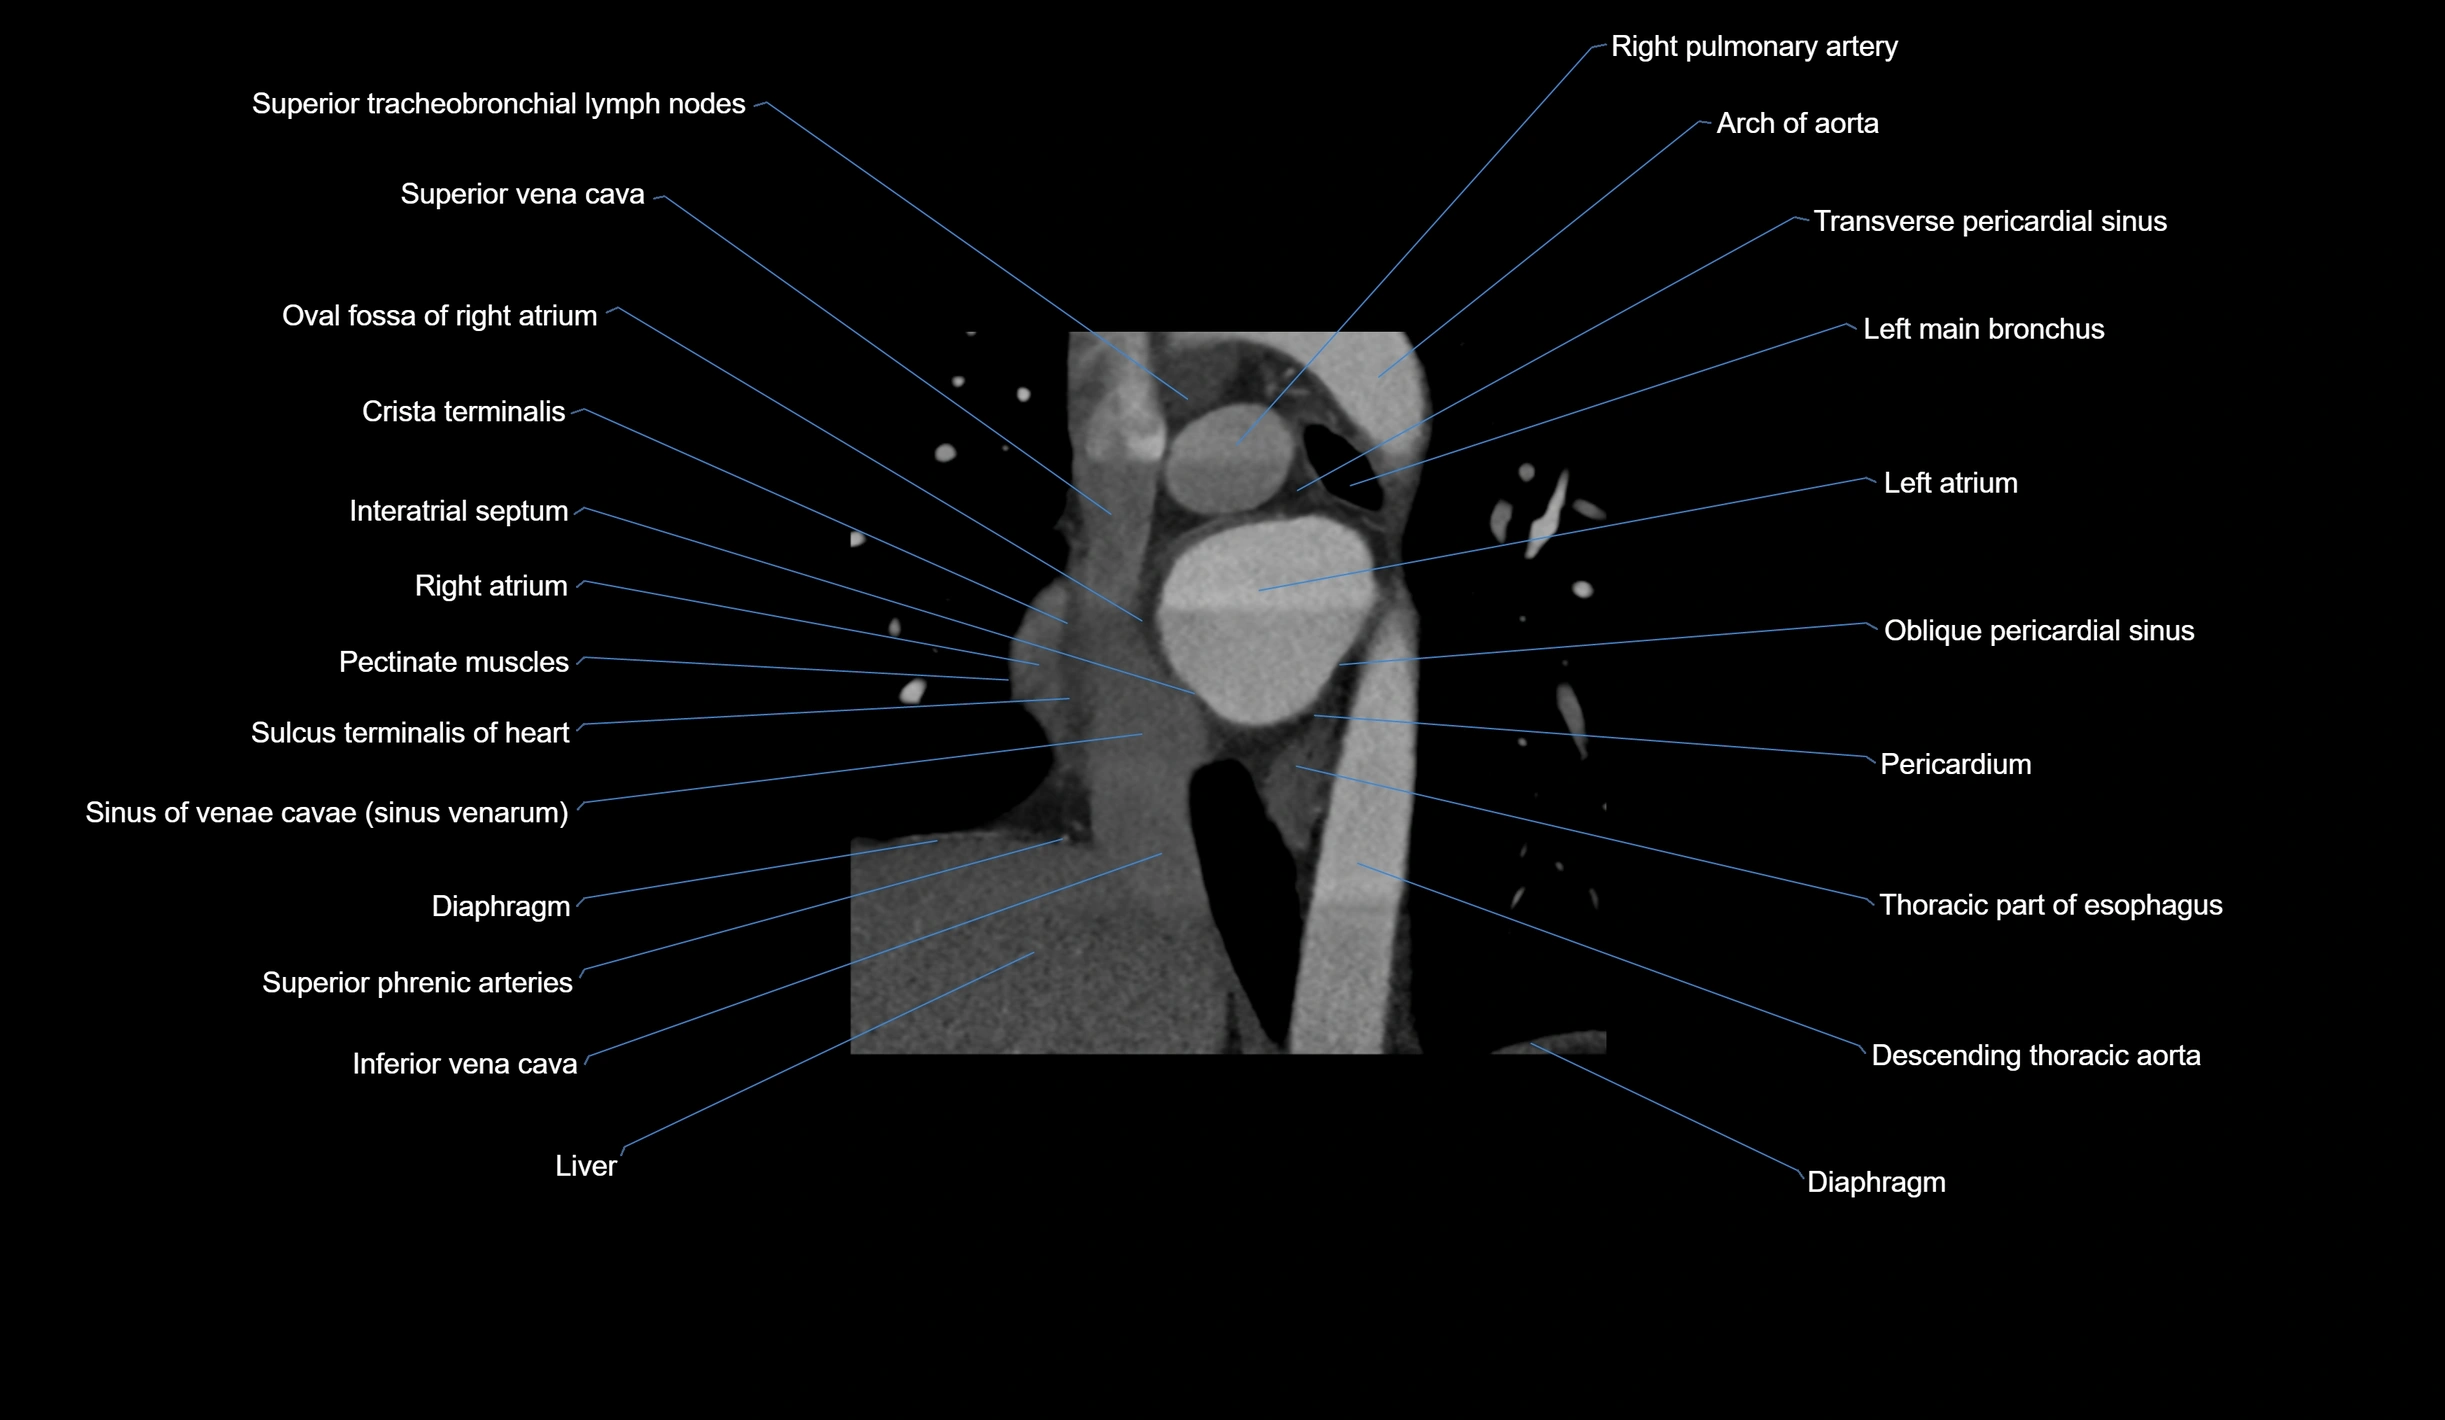

- Arch of aorta

- Diaphragm

- Inferior vena cava

- Left main bronchus

- Oblique pericardial sinus

- Oval fossa of right atrium

- Pectinate muscles

- Pericardium

- Sinus of venae cavae (sinus venarum)

- Sulcus terminalis of heart

- Superior tracheobronchial lymph nodes

- Superior vena cava

- Transverse pericardial sinus